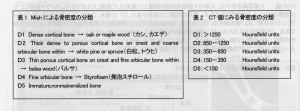

その際、クリニックでは、院内で撮影したCTをインプラント治療シュミレーションソフトで分析し、下記のような評価法と対比させ、骨の状態を判断に用いています。

骨の評価を5段階に分類し、その情報をもとに、手術方法を微妙に変化させます。